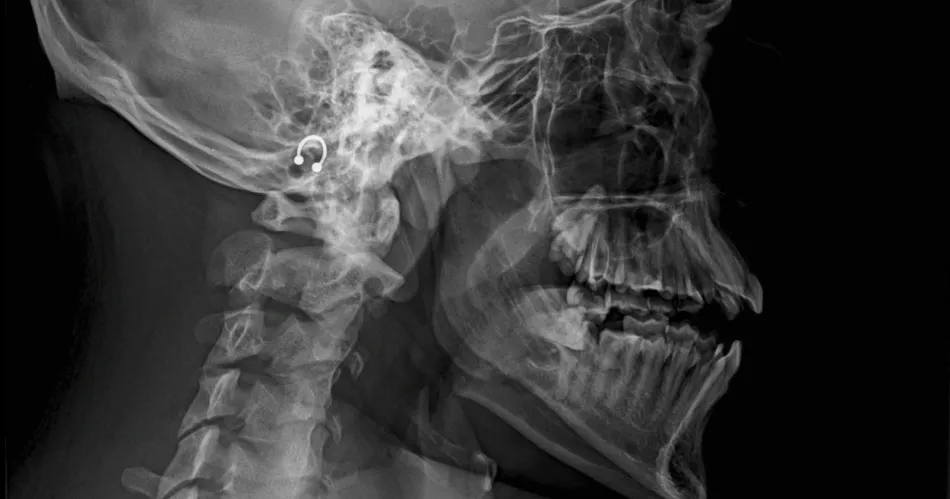

"Doble fractura de mandíbula con desplazamiento de piezas dentarias (comprometidas)". El diagnóstico corresponde a un joven que protagonizó un entredicho en una cancha de fútbol 5, ocasión en la que habría sido agredido por dos rivales, en especial uno de ellos que lo atacó de atrás.

"Me contó que después, siguieron golpeándolo. Intervinieron amigos de su equipo y pudieron contenerlos. Sangrando, llevaron a mi hijo al Hospital Independencia. Lo asistieron, contuvieron la sangre, pero tiene doble fractura de mandíbula y debe ser intervenido quirúrgicamente", continuó.

"Gracias a la obra social, todo transcurre rápido. En un centro privado proyectan operarlo el 24 de noviembre. La prótesis tiene un valor económico alto, pero somos optimistas", acotó. "Mi hijo no come y tiene paralizada toda la mandíbula. Solo me dijo: "Me defendí, pero eran dos o tres...".